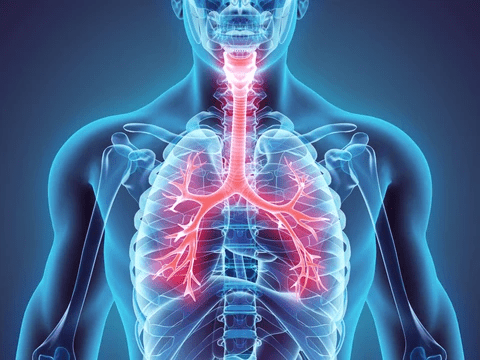

Did you know that over 23 million U.S. adults are living with asthma—and that’s just the diagnosed cases? Add in the millions more silently dealing with COPD, chronic congestion, or that nagging “can’t quite catch my breath” feeling, and you’re looking at nearly 40% of adults reporting some form of moderate to severe respiratory symptom every single day.

The Silent Breathing Crisis Hitting Adults Over 45 (And Why Most “Fixes” Fall Short)

Turning 45 often means the body starts sending quieter signals. That morning tightness in the chest. The cough that lingers after a cold. The sinus pressure that turns every deep breath into work. It’s frustrating when you mention it and hear, “It’s just aging.” Sound familiar?

Recent data shows COPD prevalence hovering around 6% for U.S. adults, climbing sharply after age 65, with women now outpacing men in some age groups. Asthma affects nearly 10% of adults overall, but the real story is the overlap—post-viral sensitivity, allergies, reflux, and environmental triggers stacking up quietly. You’ve probably tried the usual suspects: over-the-counter antihistamines that leave you drowsy, expensive air purifiers, or cutting out dairy on a friend’s advice. They help some people for a while… until they don’t.

Here’s the plot twist most articles skip: Not every breathing struggle is the same. Asthma attacks need fast medical action. COPD requires ongoing management. Seasonal congestion might respond to simple steam. Treating them all with one “miracle weed” is where things go wrong fast.